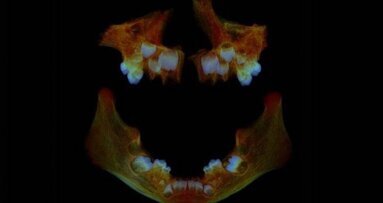

LONDON, UK: Though the relative benefits of chewing gum are often subject to debate, a number of studies have shown that the sugar-free varieties can promote oral health. On this topic, a recent review has found some evidence that chewing sugar-free gum could help to reduce the further development of dental caries in both adults and children.

The research team found that chewing sugar-free gum reduces the incidence of dental caries by 28% and that it could be used as a possible preventive agent in combination with oral health education and supervised toothbrushing initiatives. However, the researchers were quick to clarify that their findings were far from definitive for a number of reasons.